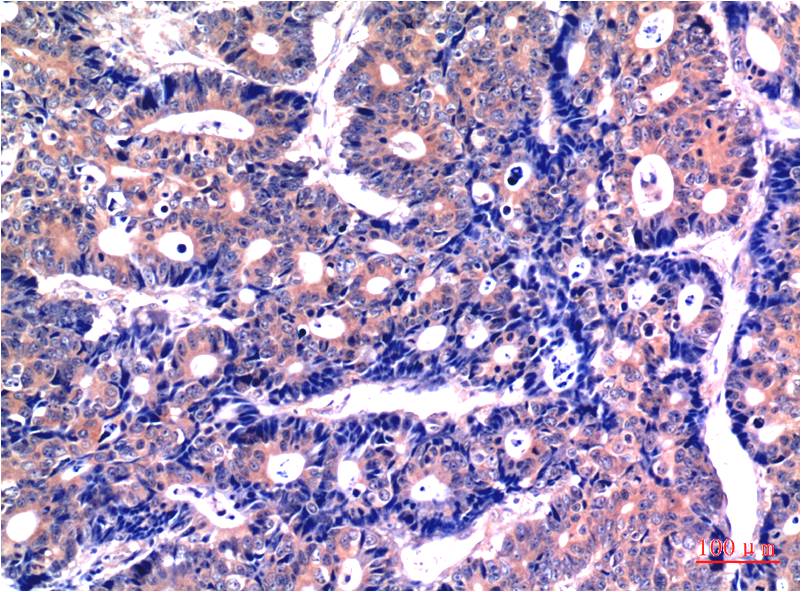

WB, IHC

Human, Rat, Mouse

WB 1:1,000-2,000 IHC 1:100-200